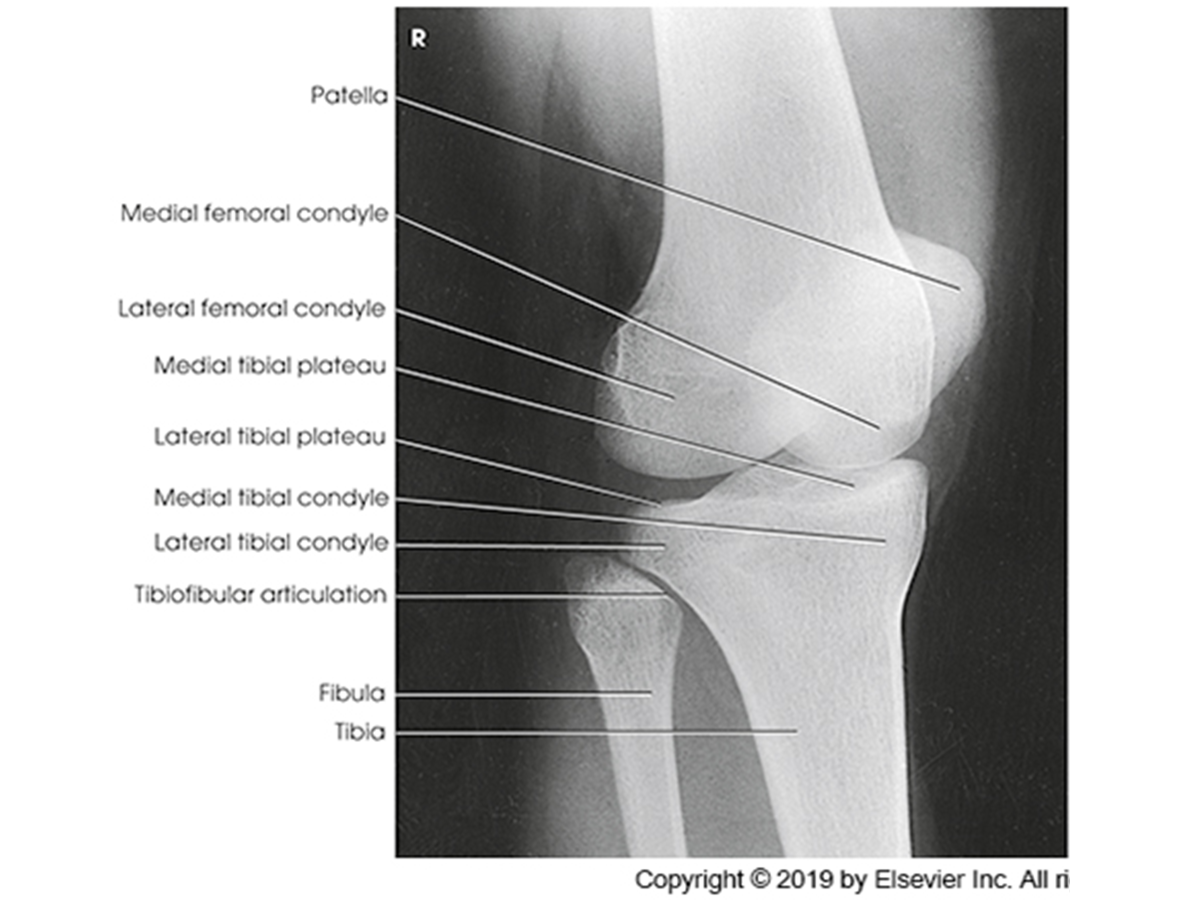

Anatomy of the knee